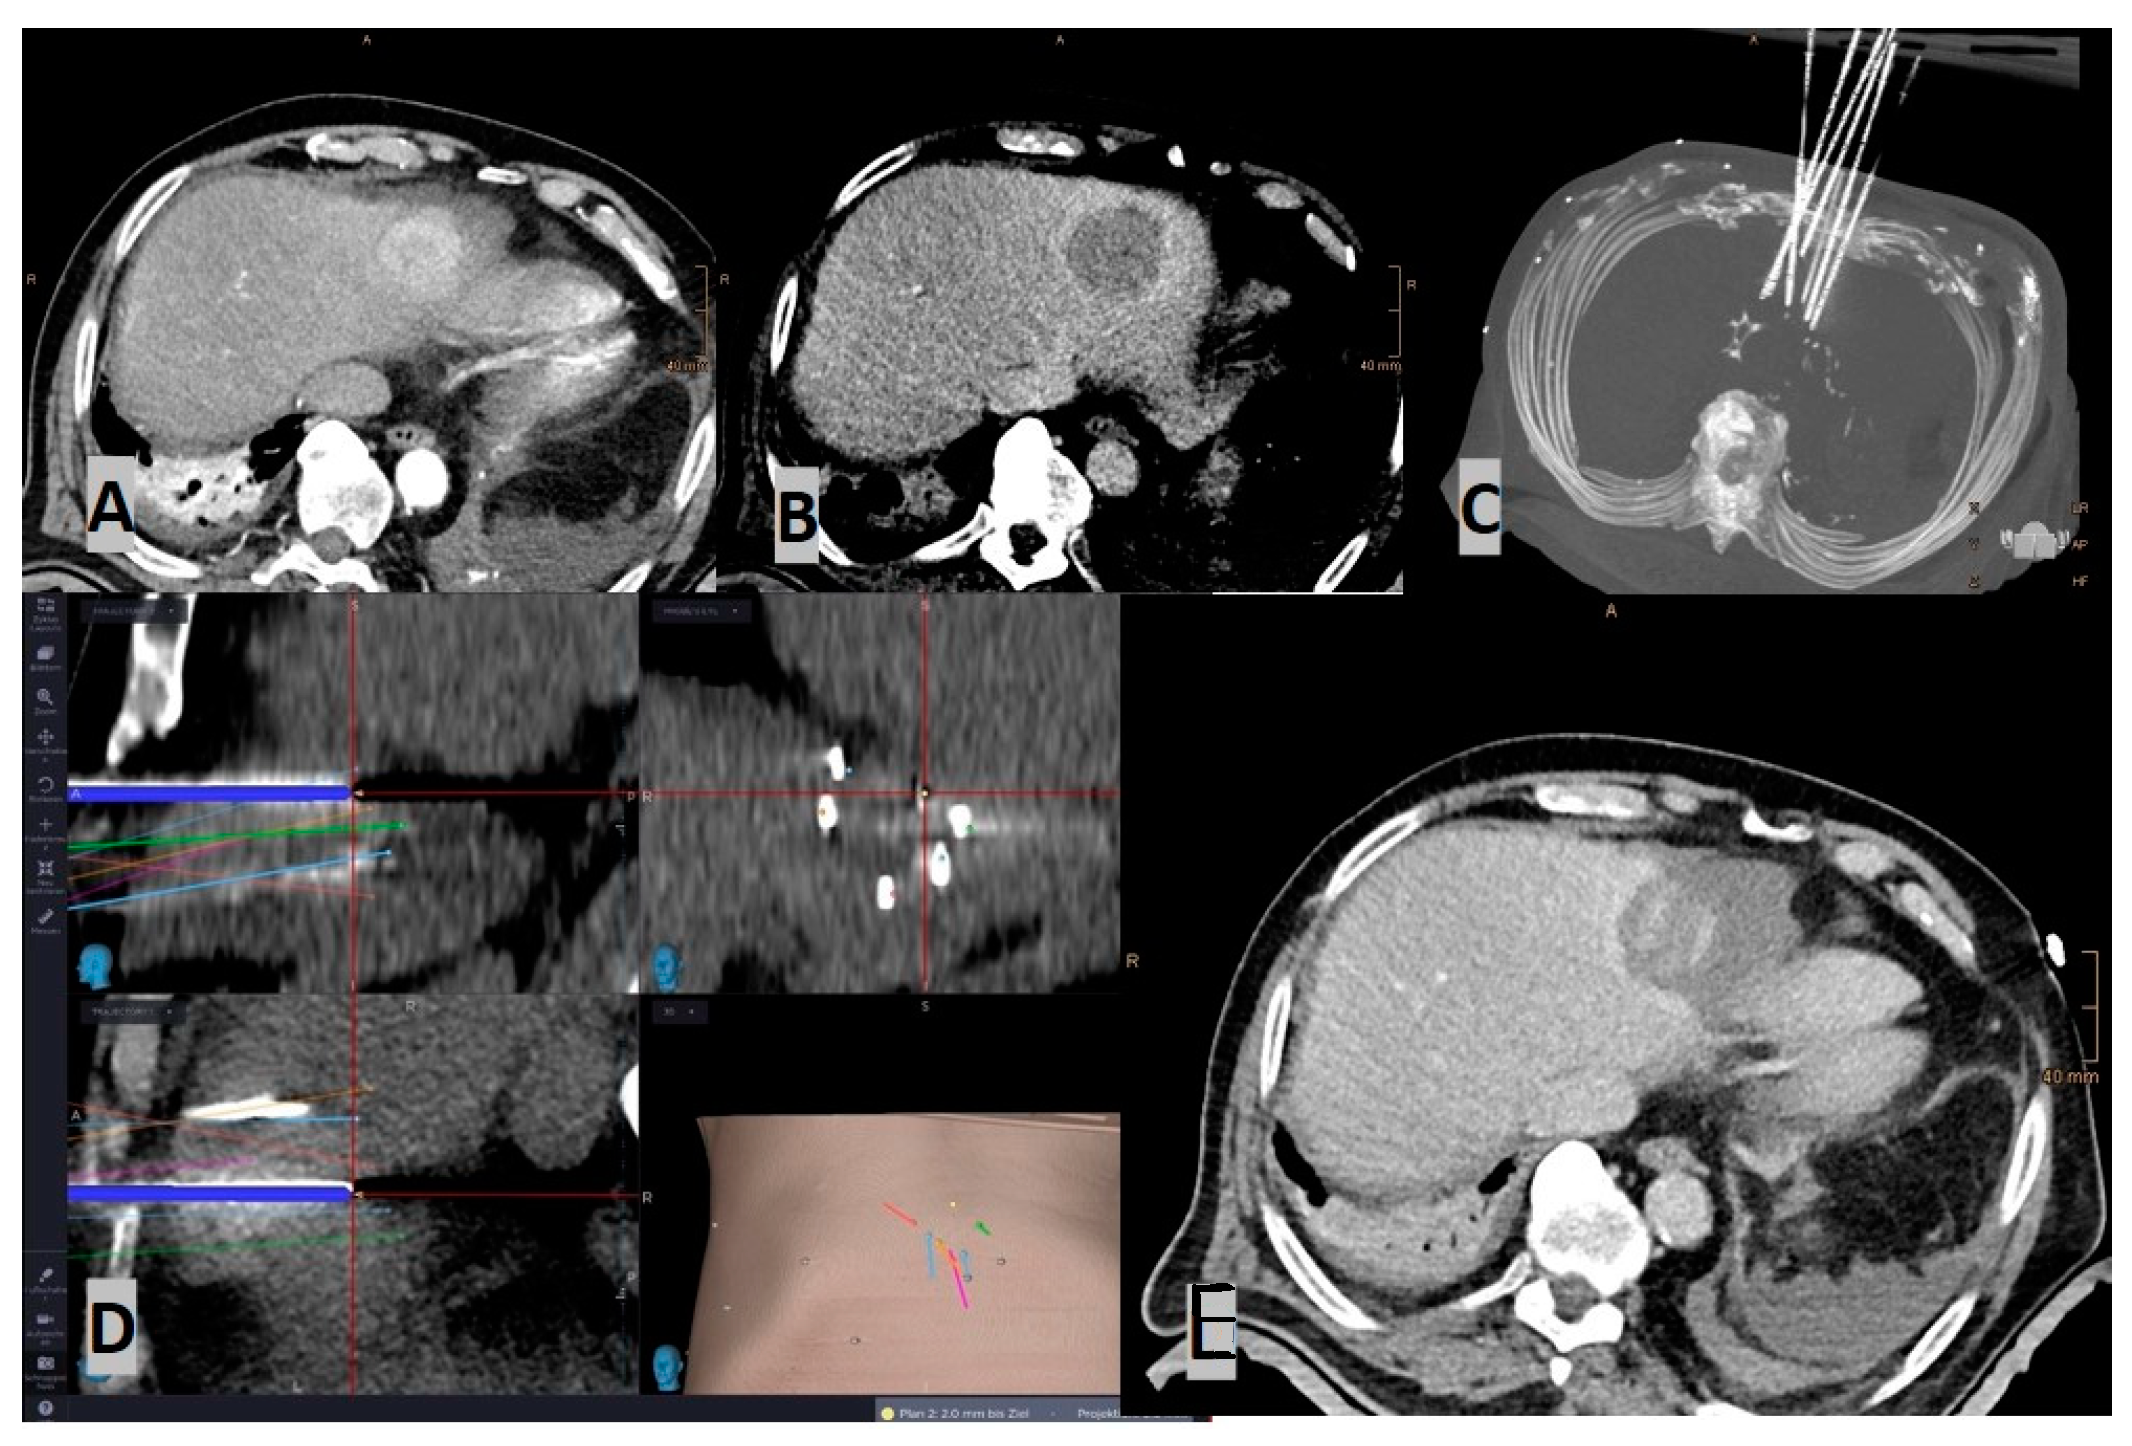

- Laimer, G.; Schullian, P.; Bale, R. Stereotactic Thermal Ablation of Liver Tumors: 3D Planning, Multiple Needle Approach, and Intraprocedural Image Fusion Are the Key to Success-A Narrative Review. Biology 2021, 10, 644. [Google Scholar] [CrossRef]

- Laimer, G.; Schullian, P.; Jaschke, N.; Putzer, D.; Eberle, G.; Alzaga, A.; Odisio, B.; Bale, R. Minimal ablative margin (MAM) assessment with image fusion: An independent predictor for local tumor progression in hepatocellular carcinoma after stereotactic radiofrequency ablation. Eur. Radiol. 2020, 30, 2463–2472. [Google Scholar] [CrossRef]

- Laimer, G.; Jaschke, N.; Schullian, P.; Putzer, D.; Eberle, G.; Solbiati, M.; Solbiati, L.; Goldberg, S.N.; Bale, R. Volumetric assessment of the periablational safety margin after thermal ablation of colorectal liver metastases. Eur. Radiol. 2021, 31, 6489–6499. [Google Scholar] [CrossRef]

- Schullian, P.; Laimer, G.; Johnston, E.; Putzer, D.; Eberle, G.; Scharll, Y.; Widmann, G.; Kolbitsch, C.; Bale, R. Technical efficacy and local recurrence after stereotactic radiofrequency ablation of 2653 liver tumors: A 15-year single-center experience with evaluation of prognostic factors. Int. J. Hyperth. 2022, 39, 421–430. [Google Scholar] [CrossRef]

- Schullian, P.; Johnston, E.W.; Putzer, D.; Eberle, G.; Laimer, G.; Bale, R. Safety and efficacy of stereotactic radiofrequency ablation for very large (≥8 cm) primary and metastatic liver tumors. Sci. Rep. 2020, 10, 1618. [Google Scholar] [CrossRef] [PubMed]

- Schullian, P.; Laimer, G.; Johnston, E.; Putzer, D.; Eberle, G.; Widmann, G.; Scharll, Y.; Bale, R. Reliability of Stereotactic Radiofrequency Ablation (SRFA) for Malignant Liver Tumors: Novice versus Experienced Operators. Biology 2023, 12, 175. [Google Scholar] [CrossRef]